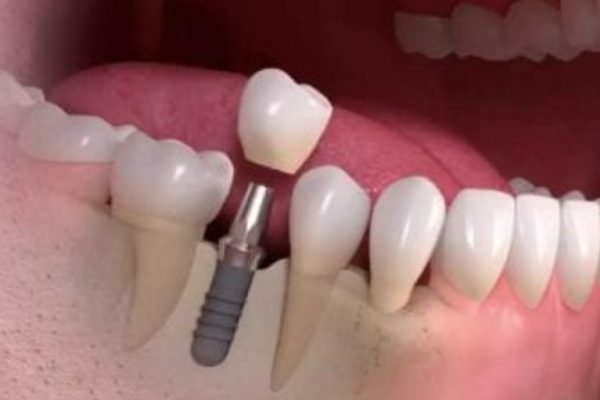

잘 결합되었다면 Abutment를 Fixture에 연결하여 잇몸 위로 돌출시킵니다. - 인상채득:

- 크라운이 제작되면(약 1주일 소요) 최종 크라운을 어버트먼트에 부착합니다.

- 이를 통해 임플란트 치아가 완전히 회복되어 환자가 정상적인 미소를 지을 수 있게 됩니다.